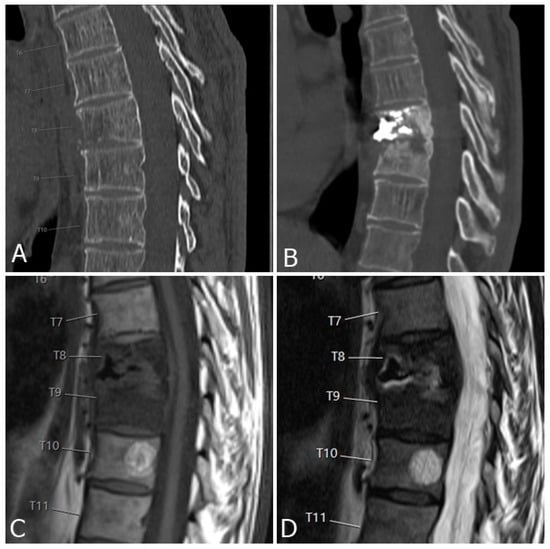

3.2. New Vertebral Fractures